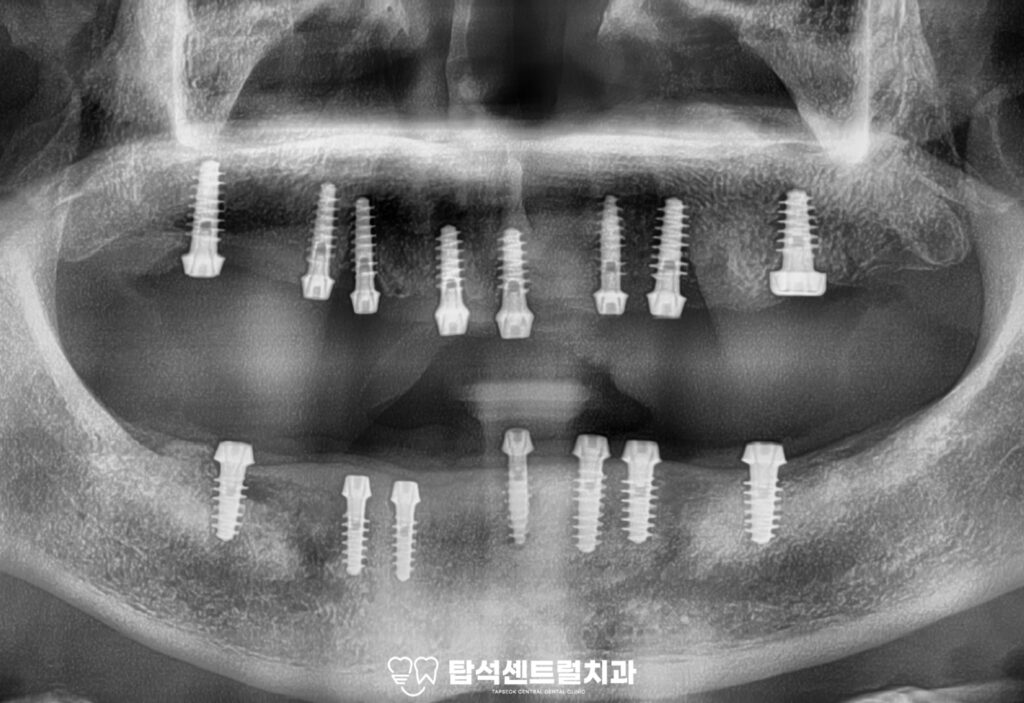

전체 임플란트 치료의 마지막 단계로,

최종 보철을 장착하였습니다.

발치 후 3개월 동안의 골유착 기간을 거쳐

고정력을 확보하였으며

임시보철을 사용하면서 적응된

치아의 고경과 높이에 맞춰

최종 보철이 정밀하게 제작된 모습입니다.